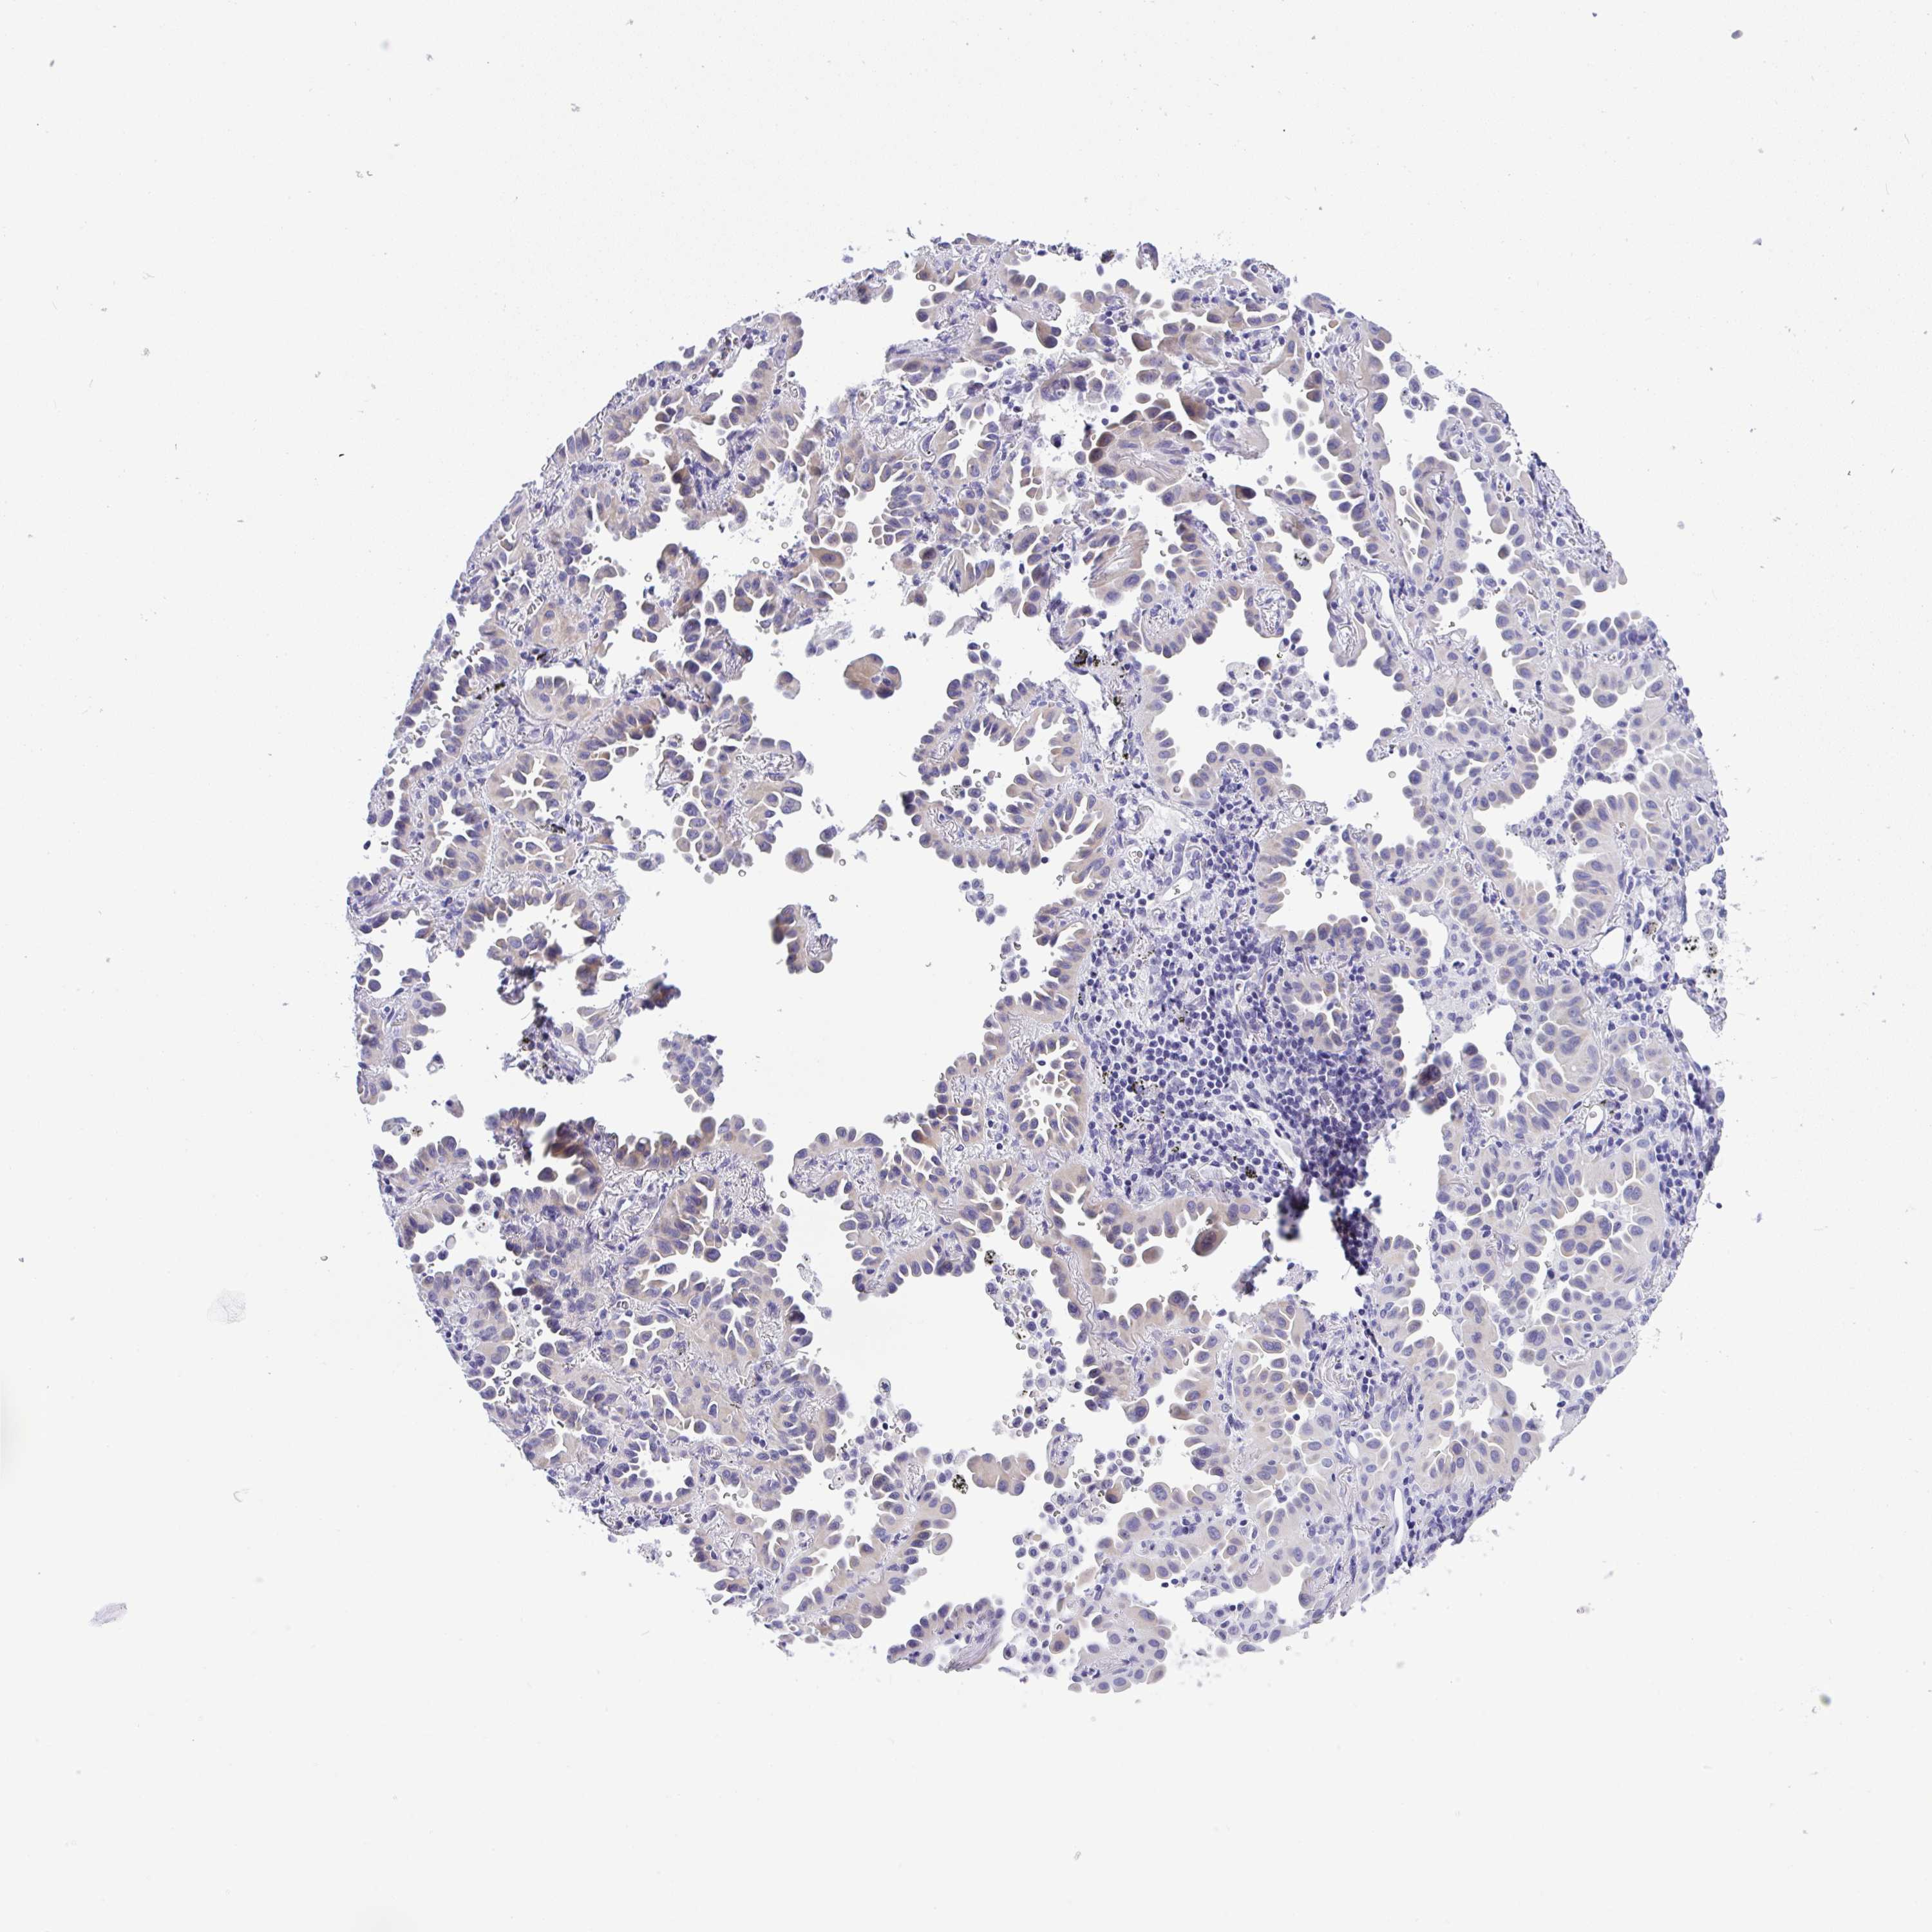

CANCER LUNG CANCER Show tissue menu

LUAD TCGA LUAD VALIDATION LUSC TCGA LUSC VALIDATION PROTEIN LUAD CPTAC PROTEIN LUSC CPTAC PROTEIN EXPRESSION